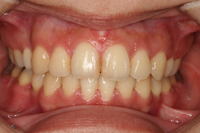

矯正の症例

| 【Before】 | 【After】 | |